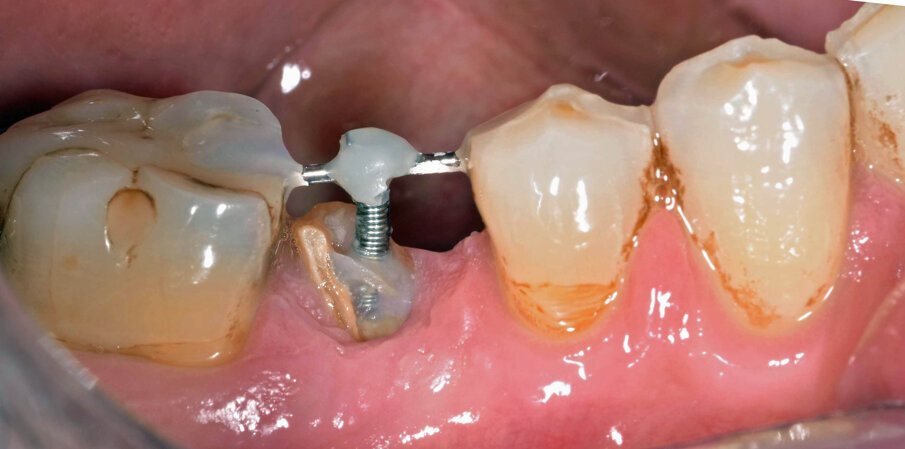

Per ottenere questo risultato nel gennaio 2021 è stato ancorato un segmento di arco in acciaio a sezione quadrata 0.021” x 0.025” agli elementi 4.4 e 4.6 per mezzo di composito. Il segmento è servito da ancoraggio per una molla con forza di trazione 150 g in posizione obliqua in senso disto-mesiale.

L’estrusione completa del frammento ha richiesto un tempo di 6 mesi, durante i quali è stata modificata più volte l’inclinazione della molla per evitare che il movimento diventasse ortogonale al segmento e mantenere la traiettoria prevista. Così facendo, è stato possibile rigenerare naturalmente l’intero alveolo e inserire, dopo 3 mesi di ulteriore maturazione del tessuto, in un contesto osseo ideale e perfettamente rigenerato un impianto Syra (Sweden & Martina) di diametro 4.25 mm e lungo 11 mm.